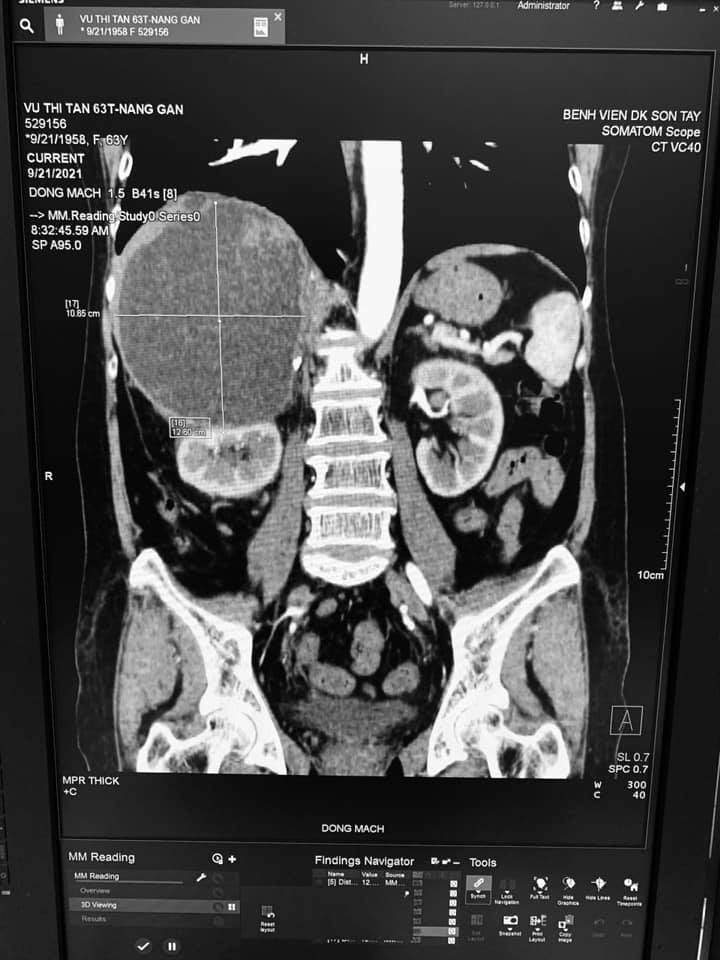

Qua hỏi bệnh, thăm khám và làm các xét nghiệm chẩn đoán cận lâm sàng được biết bệnh nhân có tiền sử Nang gan phải đã phẫu thuật nang gan 2 lần.( lần 1 năm 2019, lần 2 năm 2021), Xét nghiệm huyết học, sinh hóa các trị số bình thường, kết quả siêu âm: Hình ảnh nang gan phải TD xuất huyết trong nang, kết quả chụp cắt lớp vi tính : Hình ảnh nang gan chảy máu( KT 11x12cm).